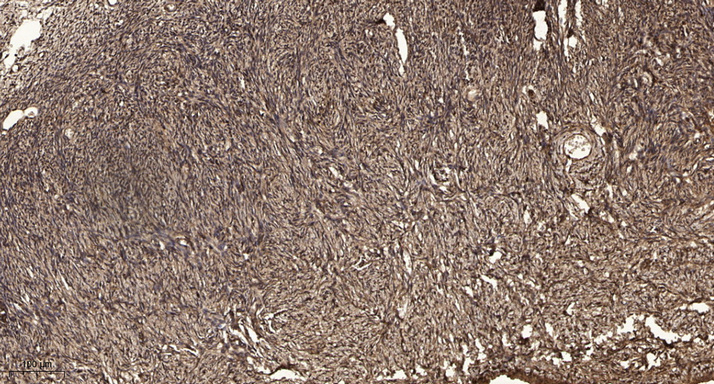

IHC (Immunohistochemistry)

(Immunohistochemical analysis of paraffin-embedded human oophoroma. 1, Antibody was diluted at 1:200(4 degree overnight). 2, Tris-EDTA,pH9.0 was used for antigen retrieval. 3,Secondary antibody was diluted at 1:200(room temperature, 45min).)